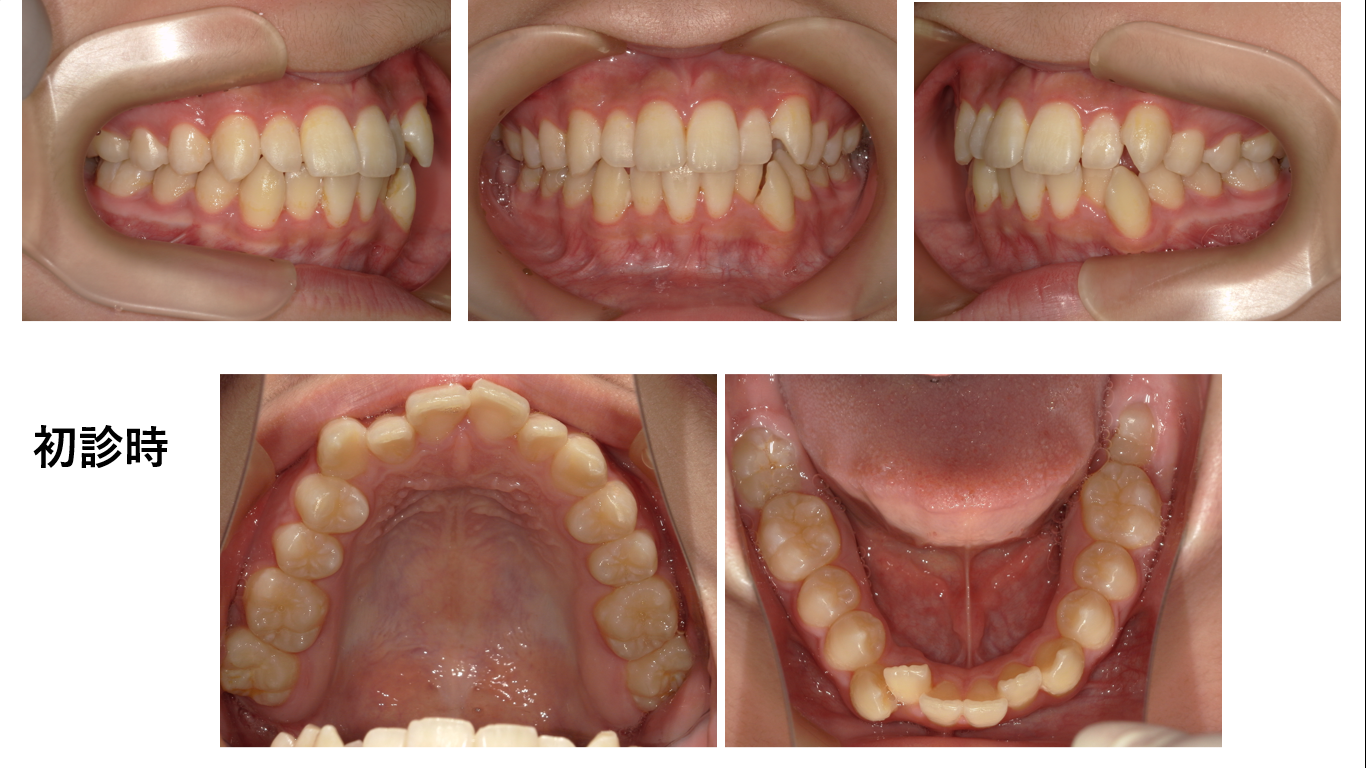

矯正症例139 AngleⅠ級叢生、下顎8番埋伏歯の牽引

初診時30歳、抜歯部位:上顎左側5番、下顎右4番,左側5番、下顎右側7番、治療期間3年7か月、治療費総額113万(税込み)上顎右側犬歯は抜歯されていました。初診の下顎右側7番が銀歯ですが、動的治療終了...